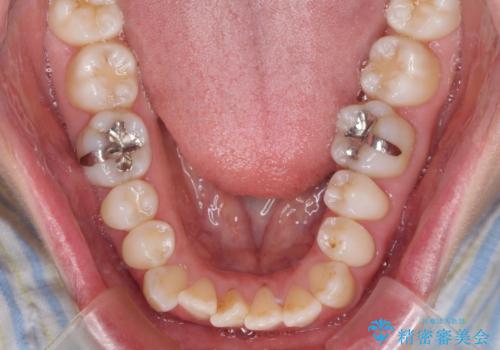

- 受け口傾向でクロスバイトの前歯を治したいとのことで来院された患者様です。

下顎骨が若干左側に変位していたため、右側にアンカースクリューを使用し、積極的に移動させながらインビザラインにて矯正治療を行うこととしました。

インビザラインによる矯正治療は、受け口傾向の治療に非常に適した方法であり、事前にシミュレーションに沿って治療を進めることできます。

今回の治療では骨格的な偏位があったためアンカースクリューを使用し、より確率の高い治療を行うことができました。